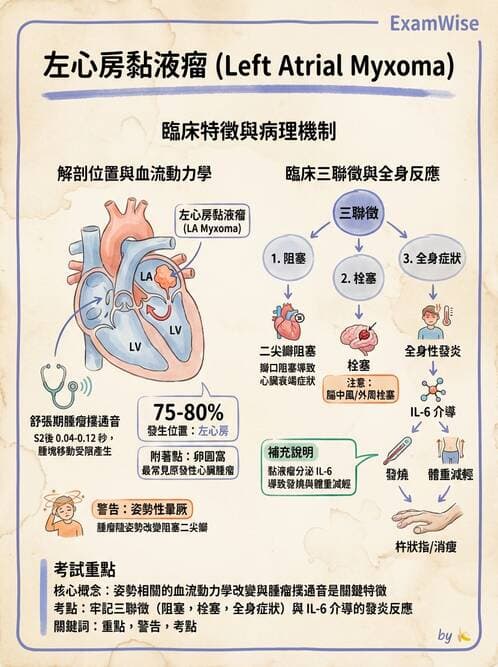

本題核心在於辨識左心房腫瘤(myxoma)所造成的功能性二尖瓣狹窄表現,包括體位相關的血流阻塞、早舒張期的低頻「tumor plop」心音,以及伴隨的全身性表現如體重減輕、乏力與杵狀指。

- 圖B(舒張期)時,影像中左心房內可見一個大而有蒂的回聲不均結構,順重力及心室舒張拉力,自左心房墜入左心室,幾近填滿二尖瓣口,顯示動態性的瓣口阻塞。

此種舒張期移動性腫塊,表徵典型左心房myxoma在舒張期經瓣口擺動致血流受限之影像表現。